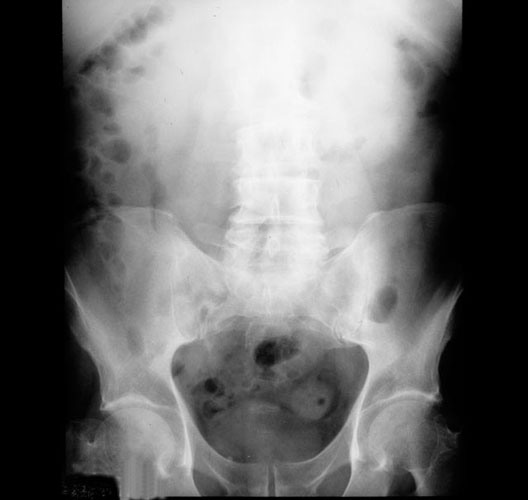

Pelvis

1. Ilium

2. Bladder

3. Pecten of pubic bone

4. Pubic symphysis

5. Iliac crest

6. Gas bubble in colon

7. Iliopubic eminence

8. Acetabular fossa

9. Head of femur

10. Superior ramus of pubic bone

11. Obturator foramen